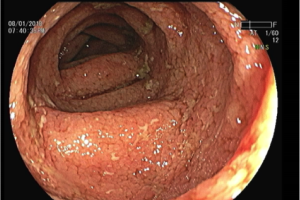

Las estadísticas indican que en la última década el cáncer colorrectal ha presentado un ascenso progresivo en cuanto a incidencia, prevalencia y mortalidad en...